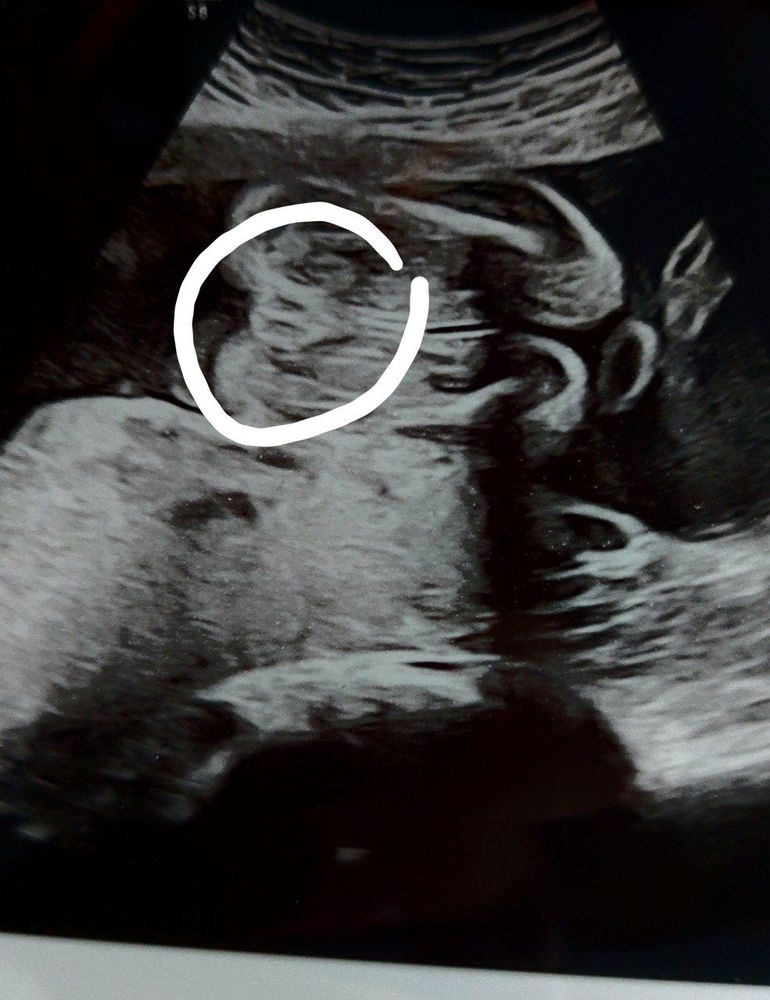

Всем привет! Первая моя беременность, на узи сказали что девочка, но все равно есть какие-то сомнения. На первом кзи в 12 нелель предположили мальчика, потом в 13.5 недель делала скрининг на генетические аномалии, в Германиион делается отдельно, то врач предположил на 90 процентов девочку. Пол нам не важен, просто интерес берет своё☺️ В 23 недель сделали второй скрининг, где врач говорит что девочка, может ли он ошибаться. Есть только такое фото))

Да,это девчуля🥰вон пирожочек такой )Это половые губы)

Врач говорит что это половые губы 😅 Думаю могла ли она ошибиться 🤷♀️☺️

Если то, на что я смотрю - половая принадлежность, то тогда девочка. Но честно, само фото вызывает вопросы, а с какой это вообще стороны 😅

Сама была удивлена такому ракурсу, врач говорит что это половые губы)

Алина Терёхина, ну если врач сказала, то тогда это оно. Она же в движении видела, ей понятно, где ноги, где голова😅. А так да, очень на половые губы похоже

Это девочка. Кофейное зёрнышко слева на фото четко просматривается 😉